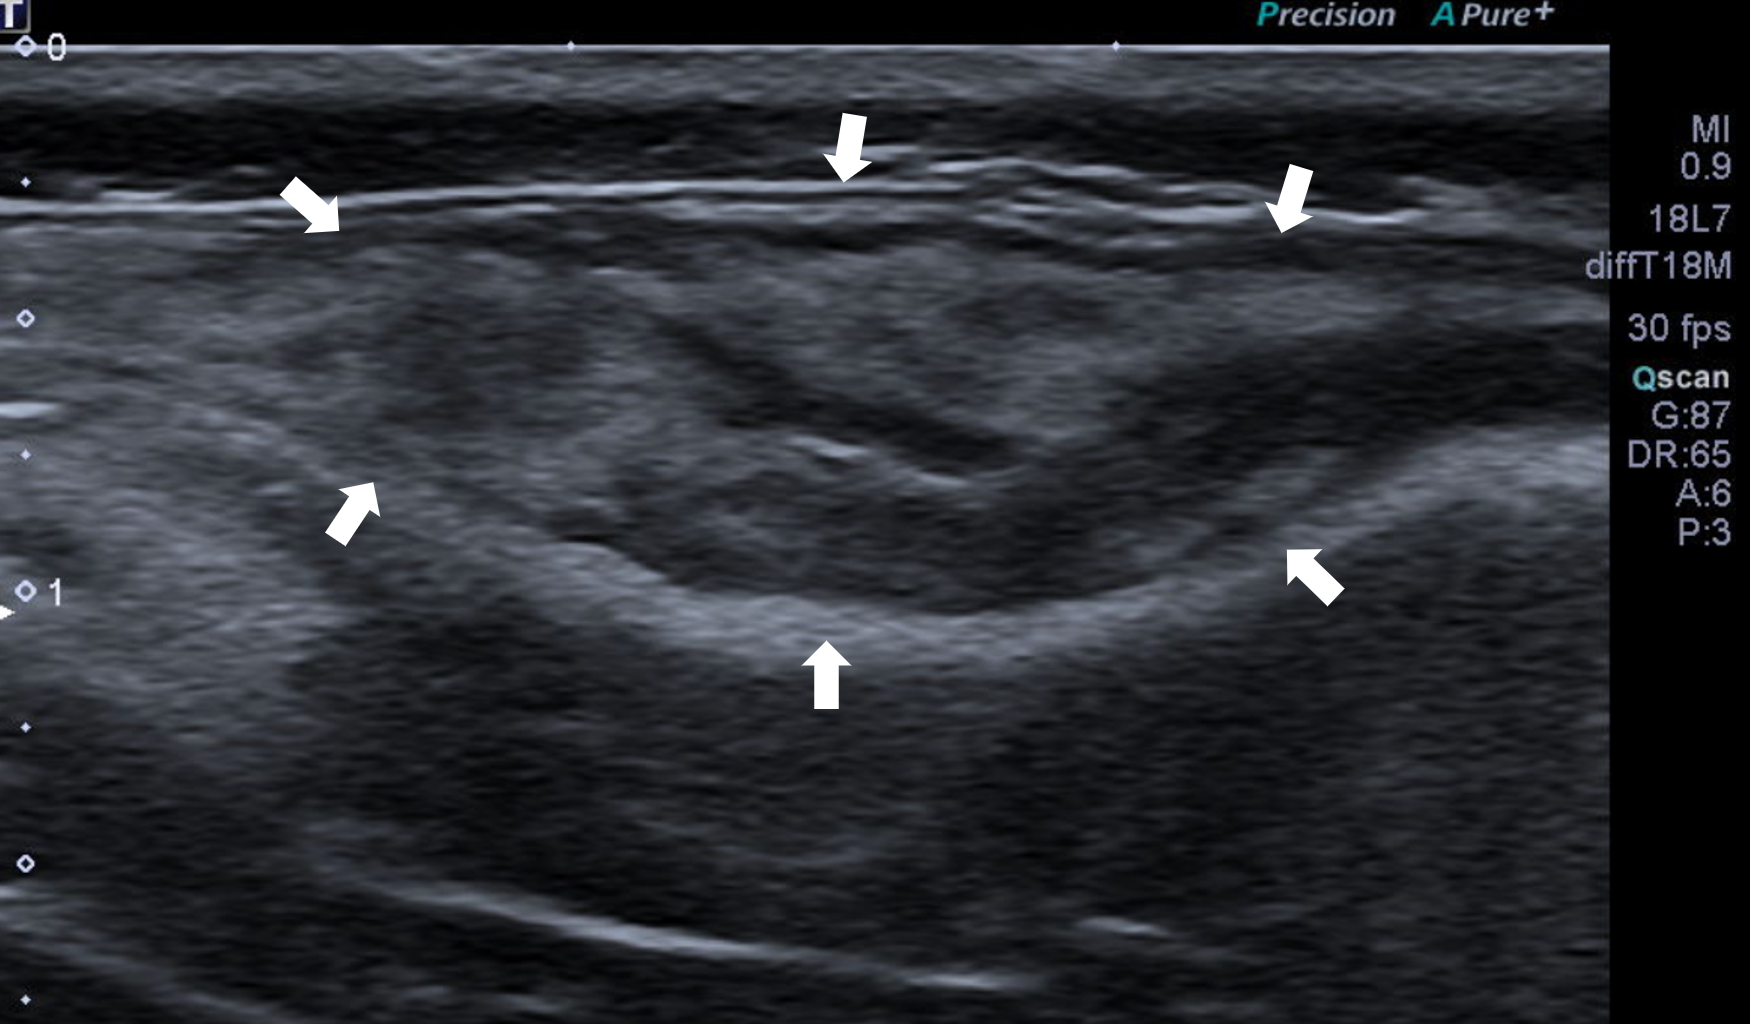

超音波

由於細針採樣後大量液體流出,團塊完全消退,導致光憑肉眼或觸診無法準確的定位團塊的位置,所以我們除了使用電腦斷層外,也以超音波輔助的方式逐步定位出團塊的12、3、6、9點鐘與更細微的邊界。

定位出邊界後,以縫線加皮釘在皮膚上做記號。